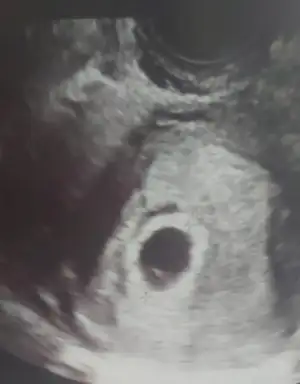

6 haftalık vajinal bi bakar mısınız size zahmet

Eklentiler

• IMG-20220430-WA0025.webp

IMG-20220430-WA0025.webp

14 KB · Görüntüleme: 81